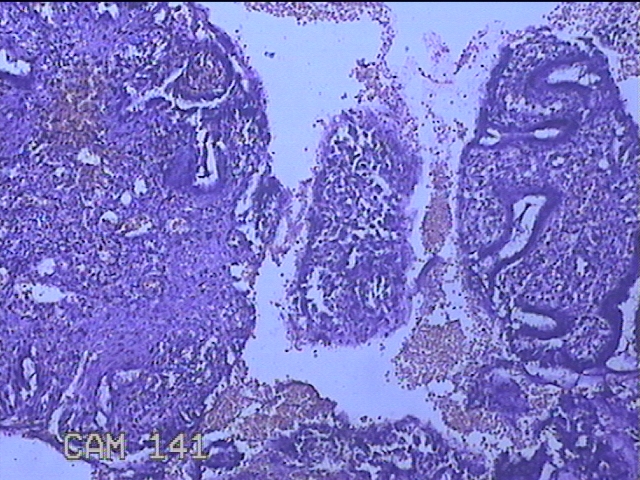

宫颈3点、9点、11点、12点组织

性别

女

年龄

37岁

临床诊断

人乳头瘤病毒感染

一般病史

HPV其他12型阳性

标本名称

大体所见

1.“宫颈3点组织”:灰白粉红色组织1x0.8x0.2cm一块。 2.“宫颈9点组织”:灰白粉红色组织0.7x0.5x0.2cm一块。 3.“宫颈11点组织”:灰白粉红色组织0.8x0.5x0.2cm一块。 4.“宫颈12点组织”:灰白粉红色组织8.5x0.5x0.2cm一块。